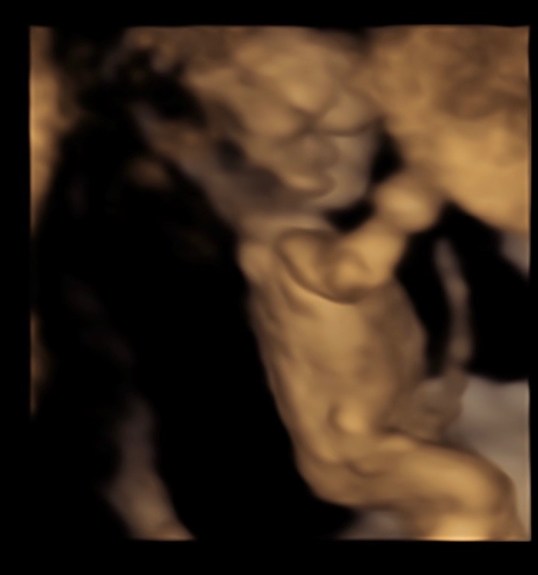

At 13 weeks, Jeff was out of town so my mom came with me to the OB ultrasound. Baby was measuring on track and moving around like crazy! This was the absolute best Valentines gift I could have ever received.